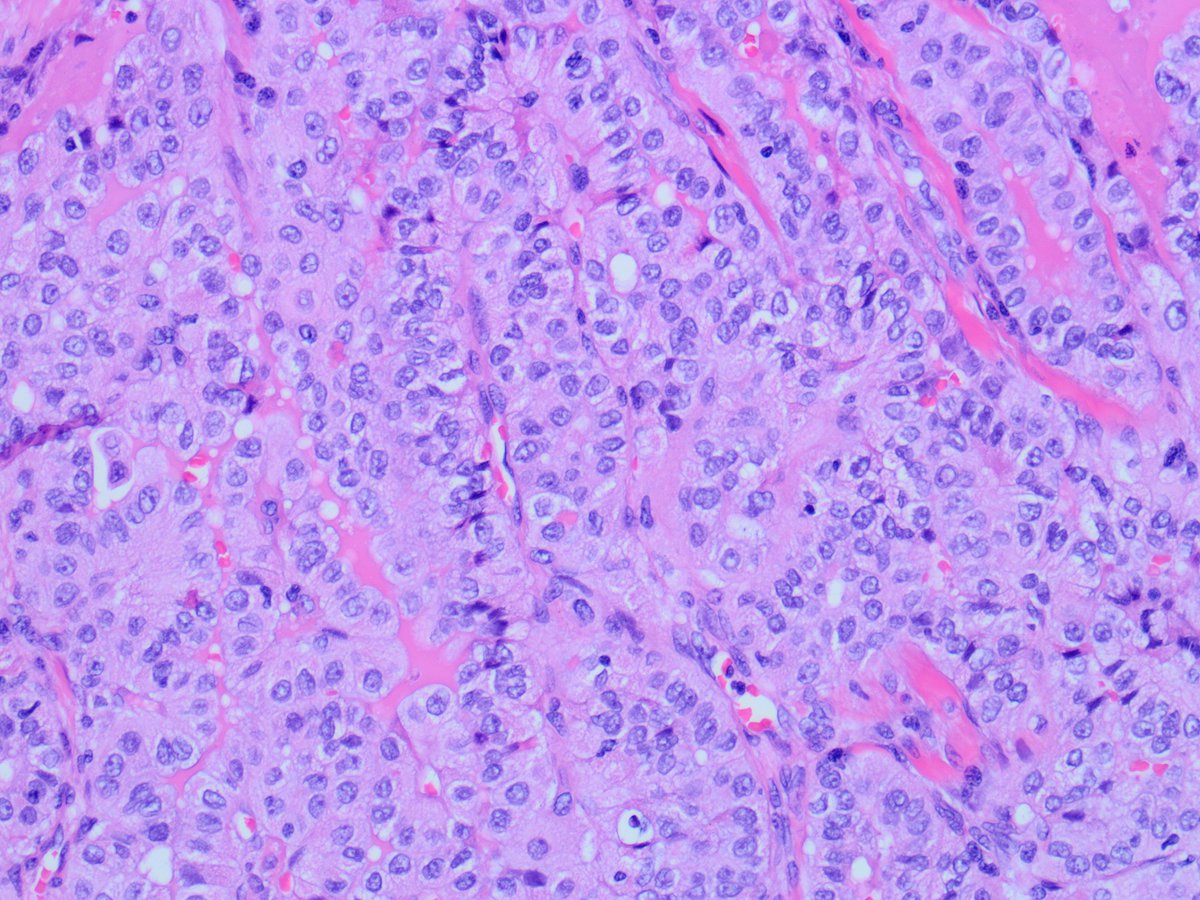

Case of the Week, submitted by our very own Dr. Huma Fatima. A 45-year-old man with a history of PTC, tall cell variant (PT3b N1a M0), s/p total thyroidectomy, central neck lymph node excision and radioactive iodine therapy, presents with new neck mass.

Some cells show tall cell morphology and rare intranuclear pseudoinclusions ("soap-bubble" appearance). These features match those seen in a previously excised cervical lymph node, consistent with metastatic tall cell variant of papillary thyroid carcinoma (PTC).

Although the sample was described as a neck mass, the presence of scattered lymphocytes suggests it is a lymph node aspirate. Cytologic features include clusters of large epithelioid cells with moderate cytoplasm and tapered tails, and atypical cells with granular cytoplasm.

Diagnostic features include: Increased tall tumor cells, especially at the periphery of clusters Granular cytoplasm with distinct borders Cytoplasmic tails and cuffs Occasional intranuclear pseudoinclusions, which are specific when present.

Tall cell variant of PTC is a more aggressive subtype of the most common thyroid malignancy, with higher recurrence risk than classic PTC. Preoperative or cytologic recognition is important for treatment planning.

The patient received radioactive iodine but no radiotherapy, and iodine does not induce radiotherapy-like cytologic changes. The cytomorphology strongly supports tall cell variant of PTC, with metastasis to a cervical lymph node, being the most likely diagnosis.

Despite the tissue culture-like appearance that might mimic reactive fibroblasts, the clinical setting, nuclear pleomorphism, cellular aggregates, and epithelioid cells in a lymphoid background support a diagnosis of metastasis over a reparative process.